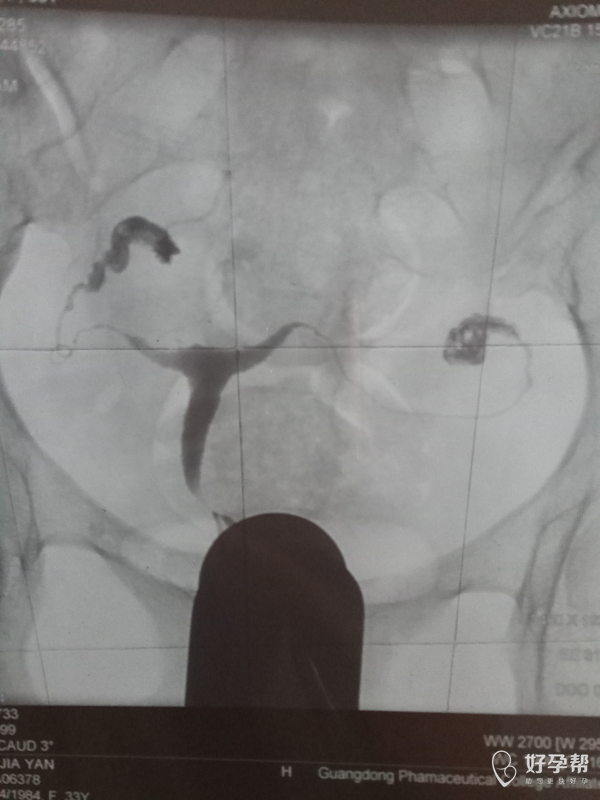

医生帮我看看造影照片,

这是碘油造影吧,双侧输卵管都是通畅的,建议积极试孕,祝好孕